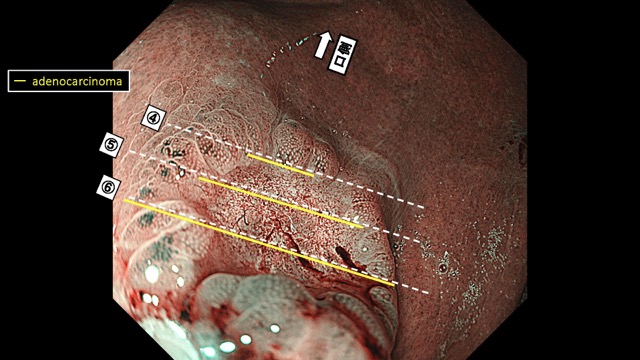

胃002